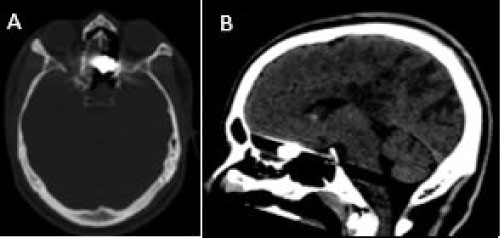

A 23-year-old male admitted with firearm injury to his head in the left occipital region by a friend while playing video games. In his physical examination, there was a single entry wound situated on the left side of the occipital bone, the exit wound could not be found. In the first neurological examination, the patient had headache and GCS at the time of admission was 14. Pupils were equally reactive, and his vitals were stable. On physical exam, he was awake and alert, in no apparent distress. Patient had no speech disorders neither cognitive or ambulation impairment. The only symptom was right hemianopsia. Cranial computerized tomography (CT) (Figure 1) revealed gunshot wound through the posterior left parietal cranium and the underlying left parietal lobe, resulting in a comminuted fracture with multiple bone fragments and metal fragments within the left posterior parietal lobe. A metallic bullet (13.9 mm L × 10 mm T × 13.2 mm AP) within the left posterior parietal parenchyma and moderate volume subarachnoid hemorrhage throughout the parieto-occipital region. It also demonstrates few punctate foci of intraparenchymal contusions within the left parieto-occipital region and small volume left posterior parietal subdural hematoma. The entry wound was debrided and sutured. The patient was treated conservatively with antibiotics, antiepileptics, and anti-edema drugs.

Figure 1: First CT revealed gunshot wound through the posterior left parietal cranium and the underlying left parietal lobe, resulting in a comminuted fracture with multiple bone fragments and metal fragments within the left posterior parietal lobe. A metallic bullet within the left posterior parietal parenchyma. A) Axial bone window; B) Sagittal brain window; C) 3D VR. View Figure 1